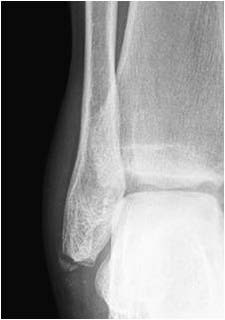

You have had a simple soft tissue injury to your ankle/foot, as part of this you may also have a chipped bone.